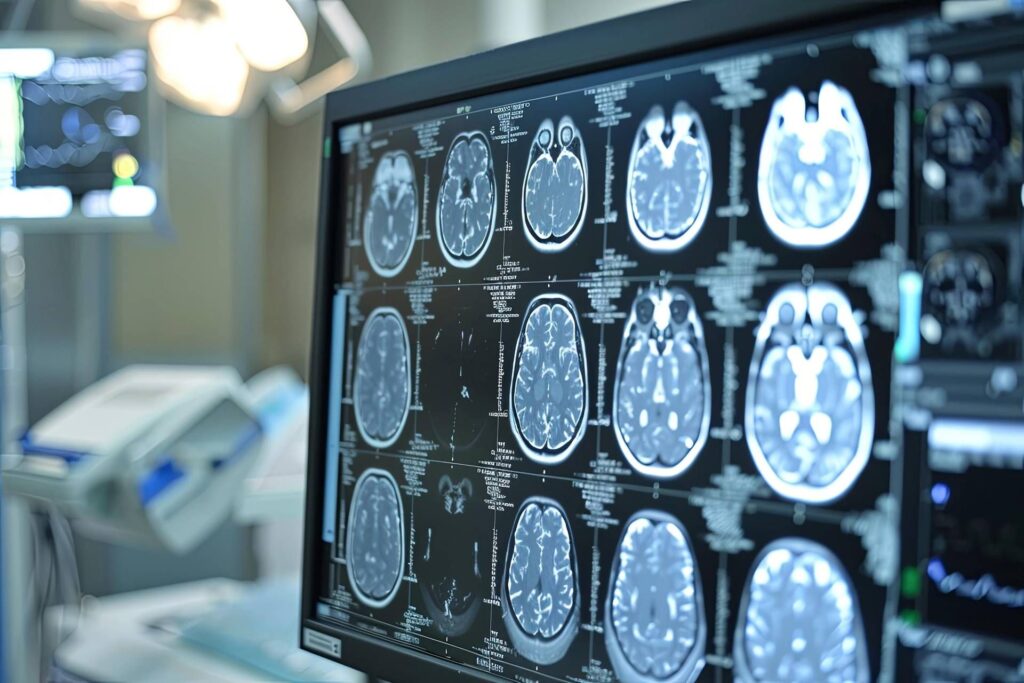

Negli ultimi anni la ricerca ha ottenuto risultati importanti, introducendo farmaci innovativi e biomarcatori che migliorano la diagnosi precoce della demenza. Questi strumenti offrono la possibilità di individuare la malattia in una fase iniziale, aumentando le chance di rallentare il decorso e migliorare la qualità della vita. Tuttavia, così come sottolinea Alessandro Padovani, presidente della SIN, la scoperta di nuove terapie, pur significativa, non basta a garantire un impatto reale sulla vita dei pazienti. La sfida principale resta la capacità del sistema sanitario di mettere in pratica questi risultati.

La presa in carico deve diventare un percorso completo che copra tutte le tappe, dalla prevenzione fino alla gestione delle fasi avanzate della malattia. Senza un’organizzazione adeguata, i benefici immortali rischiano di fermarsi alla ricerca senza tradursi in un miglioramento concreto. Inoltre occorre un accesso tempestivo alle cure e un intervento multidisciplinare che integri aspetti clinici con quelli cognitivi, funzionali e sociali. La separazione frammentata delle risposte non può più reggere davanti a questa malattia che coinvolge profondamente i pazienti ma anche le famiglie.

La natura dell’Alzheimer richiede oggi un’attenzione differente rispetto al passato. Non si tratta più soltanto di una condizione da accompagnare nei suoi momenti finali, ma di una patologia cronica con cui convivere a lungo. Per questo diventa necessario affrontare la malattia non solo con terapie farmacologiche, ma con un sistema assistenziale capace di accompagnare il paziente sin dalle prime manifestazioni.

La tempestività dell’intervento è diventata concreta grazie a nuovi strumenti. Sviluppare modelli integrati di assistenza sul territorio nazionale significa garantire continuità e uniformità nella presa in carico. I pazienti devono poter contare su un percorso che unisca prevenzione, diagnosi, cura e supporto per familiari e caregiver. Ogni fase va coordinata in modo da evitare discontinuità che tendono a compromettere la qualità della vita e la dignità delle persone colpite.